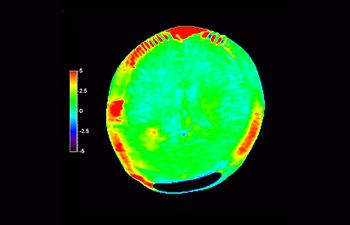

In een samenleving waarin veel neurologische aandoeningen voorkomen, streeft Philips naar een superieure duidelijkheid op het gebied van diagnoses en behandelingsbegeleiding voor alle patiënten. Hoewel MR vandaag de dag de gouden standaard is in neuro-oncologische beeldvorming, is er nog ruimte voor verbetering van de nauwkeurigheid bij het beoordelen van tumoren en follow-ups. 3D APT (Amide Proton Transfer) is een unieke, contrastvrije MR-beeldvormingsmethode voor de hersenen als antwoord op de vraag naar betrouwbaardere diagnostiek in de neuro-oncologie. 3D APT maakt gebruik van de aanwezigheid van endogene celeiwitten voor het produceren van een MR-signaal dat direct correleert met celproliferatie, een marker voor tumoractiviteit. 3D APT kan getrainde medische professionals ondersteunen bij het maken van onderscheid tussen laaggradige en hooggradige gliomen en tussen de ontwikkeling van de tumor en het effect van de behandeling1.

met 3D APT